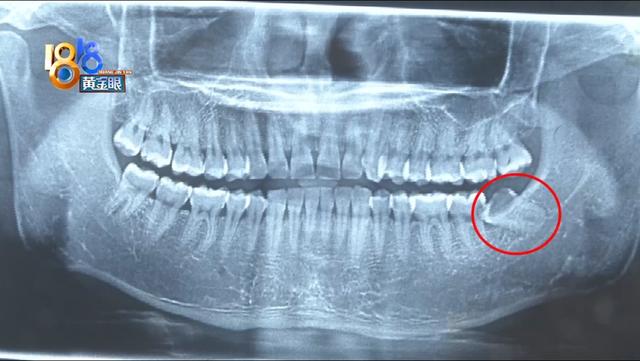

CT影像显示 , 小刘左侧下方最后一颗牙齿明显倾斜 , 顶到了相邻的后槽牙 。 按照医生的建议 , 小刘第二天一早就过来拔牙了 。

杭州市滨江区西兴街道社区卫生服务中心 卢副主任:“口腔科医生去看的时候 , 他给我们的反馈 , 是两颗牙齿都是有问题的 , 由于他现在左侧的牙齿 , 比较明显嘛 , 而且有脓肿 , 有红斑 , 不适合当天来拔牙 , 但是右边这颗牙齿显示出来是顶牢的 , 还是有问题 , 所以医生建议右边的先处理 。 ”